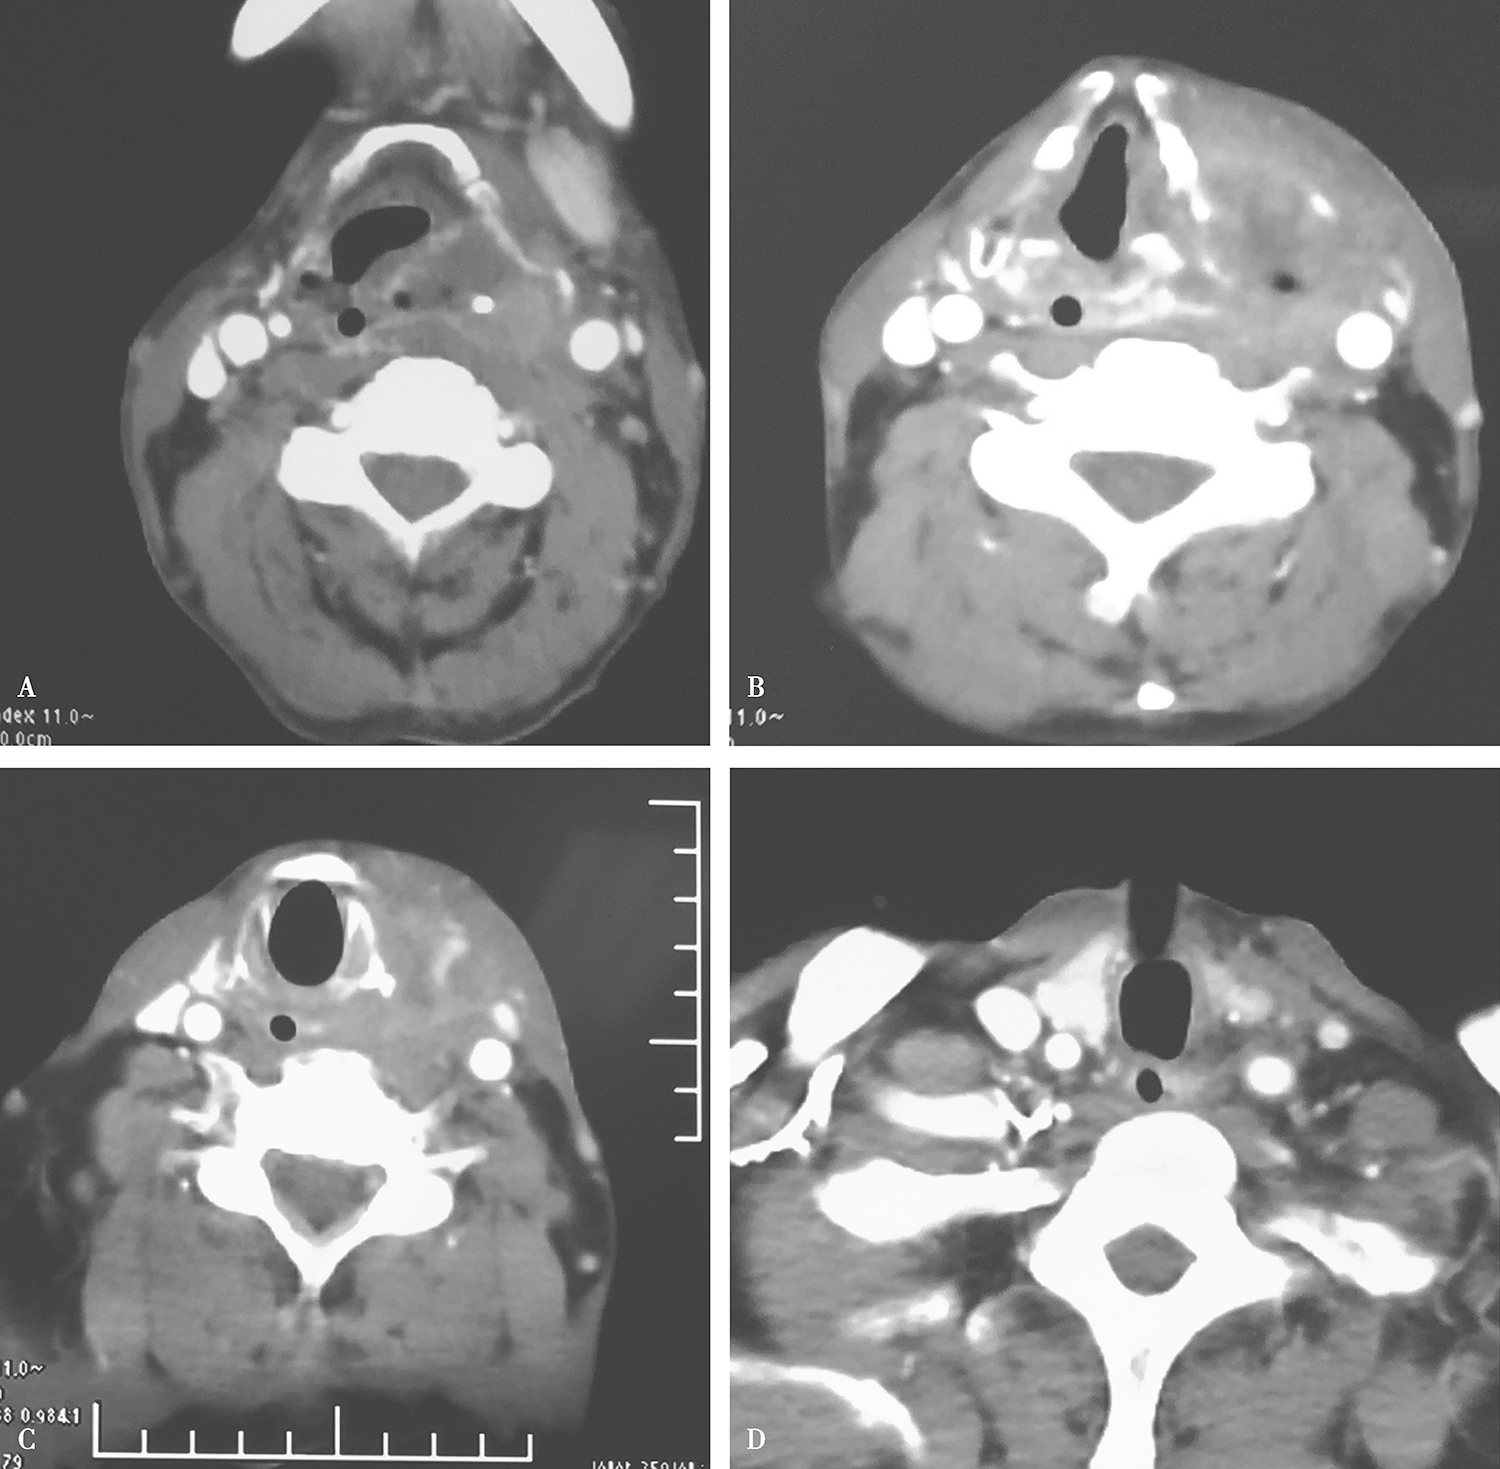

2.放化疗结束后行颈胸强化CT,见患者原发灶及颈部淋巴结退缩较明显,达到小PR,颈部转移淋巴结与颈动脉鞘粘连减轻(图5)。入住头颈外科行计划性放疗后挽救性手术治疗。

图5颈胸部增强CT示患者原发灶及颈部淋巴结退缩较明显,颈部转移淋巴结与颈动脉鞘粘连减轻